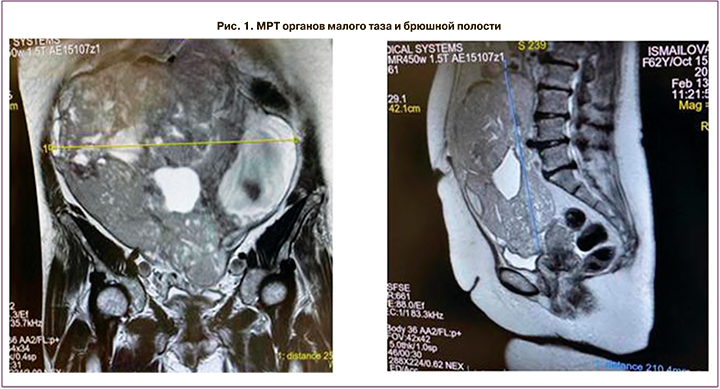

Магнитно-резонансная томография (МРТ) органов малого таза: МР-картина внеорганного объемного образования в полости малого таза и брюшной полости. МР-признаки лейомиомы матки, серозометры, кисты бартолиновой железы (рис. 1).